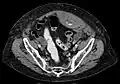

Rectus sheath hematoma as seen on ultrasound[5]